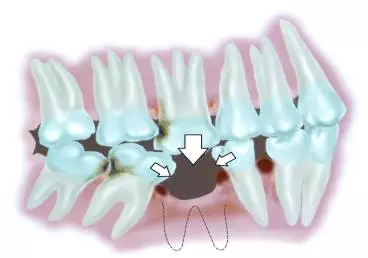

美奥王汉禹院长也表示,如果对缺牙置之不理,那么旁边的牙齿也会慢慢倾斜,牙槽骨会渐渐萎缩,咀嚼能力下降,影响营养摄入,进而影响身体健康。

如果牙齿长时间缺少牙根的支撑,牙槽骨将会严重萎缩造成牙弓走位,且支撑脸型的能力也会降低,脸部会跟着改变,比同龄人显得苍老。

所以牙齿出现缺失时候,一定要及时修复,以免造成更严重的后果。